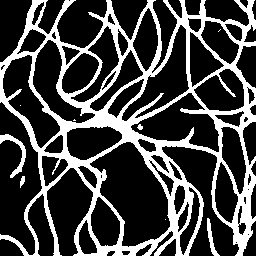

Semantic segmentation of blood vessels is an important task in medical image analysis, but its progress is often hindered by the scarcity of large annotated datasets and the poor generalization of models across different imaging modalities. A key aspect is the tendency of Convolutional Neural Networks (CNNs) to learn texture-based features, which limits their performance when applied to new domains with different visual characteristics. We hypothesize that leveraging geometric priors of vessel shapes, such as their tubular and branching nature, can lead to more robust and data-efficient models. To investigate this, we introduce VessShape, a methodology for generating large-scale 2D synthetic datasets designed to instill a shape bias in segmentation models. VessShape images contain procedurally generated tubular geometries combined with a wide variety of foreground and background textures, encouraging models to learn shape cues rather than textures. We demonstrate that a model pre-trained on VessShape images achieves strong few-shot segmentation performance on two real-world datasets from different domains, requiring only four to ten samples for fine-tuning. Furthermore, the model exhibits notable zero-shot capabilities, effectively segmenting vessels in unseen domains without any target-specific training. Our results indicate that pre-training with a strong shape bias can be an effective strategy to overcome data scarcity and improve model generalization in blood vessel segmentation.